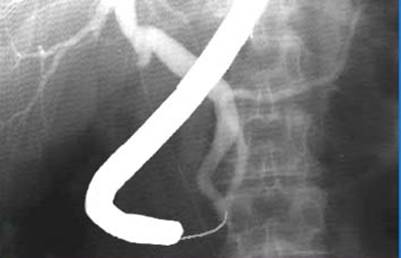

Фиброгастродуоденоскопия, как правило, выявляет вторичные изменения желудка и двенадцатиперстной кишки, которые развиваются при тяжелых деструктивных формах острого панкреатита: за счет инфильтрата и скопления жидкости в сальниковой сумке происходит сдавление этих органов извне; их слизистая обычно отечна, гиперемирована, с кровоизлияниями; нередко образуются острые язвы и эрозии. При подозрении на внутрипротоковую гипертензию, под контролем эндоскопа может быть произведена катетеризация большого дуоденального соска (рис. 12) для выполнения ретроградной холангиопанкреатографии, а при подтверждении диагноза билиарного панкреатита (при наличии механической желтухи, объективно подтвержденном расширении холедоха и при отсутствии эффекта от проводимой терапии в течение 48 часов) - эндоскопическая папиллосфинктеротомия и дренирование холедоха и главного панкреатического протока.

Рис. 12. Ретроградная холангиопанкреатография,